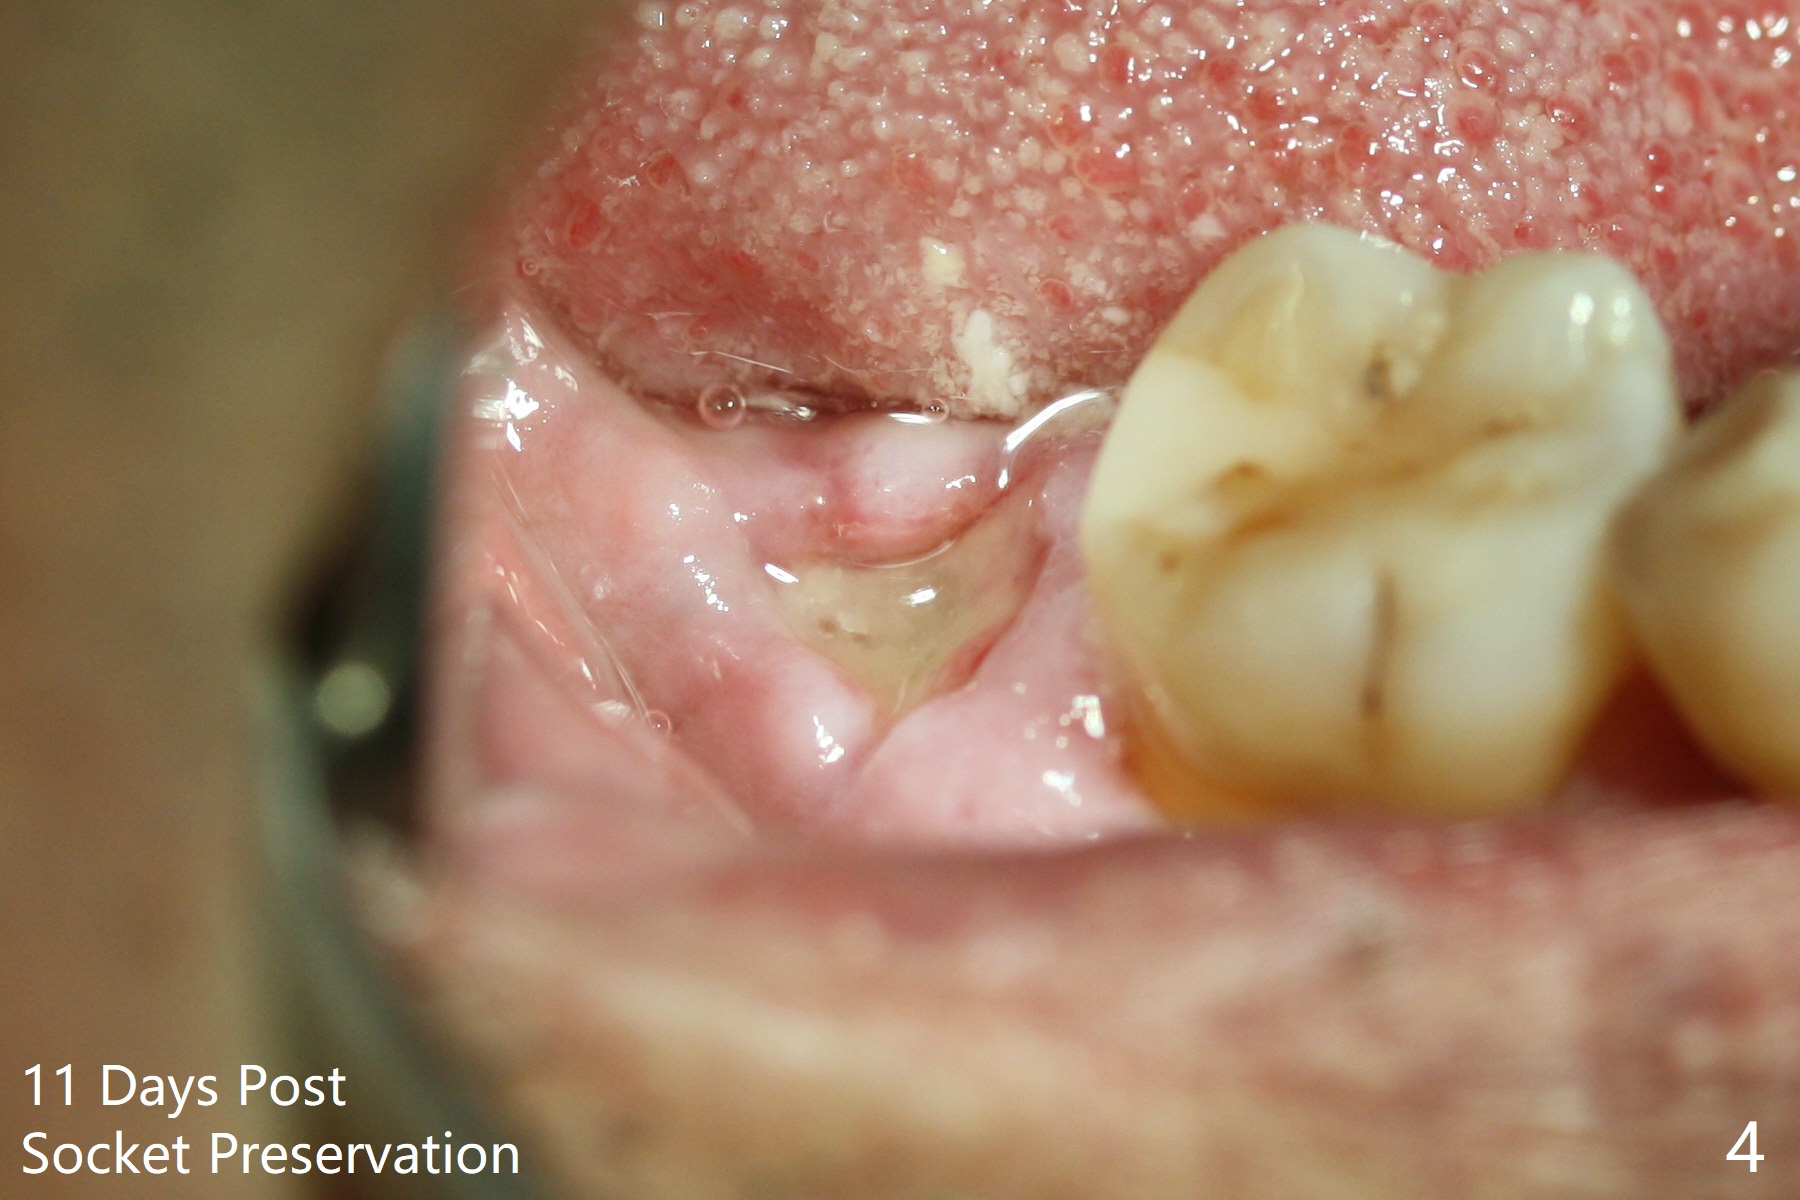

The socket shrinks with buccal plate reduction 3 months post socket preservation (Fig.5), as compared to 10 days postop (Fig.4). To restore the socket as much as possible, Magic Split is used (flapless), followed by Magic Expanders 3-3.8 mm for 11 mm (gingival level) and a 4x11mm dummy implant (Fig.6). The osteotomy is moved distal by using Lindamann bur; following 3.8 mm Magic Drill, a 4.5x11 mm dummy implant (Fig.7). Finally a definitive 5.5x9 mm implant is placed with <45 Ncm; a 6x2 mm healing abutment is placed to close the access (Fig.8). Autogenous bone harvested from the Magic Drill returns to the osteotomy mainly buccal prior to implant placement (Fig.8 *). The patient reports no discomfort immediately postop, thanks to the flapless technique. The patient has had postop pain; 11 days postop, the abutment and implant are found to be loose. After re-tightening by hand, the complex is seated deeper and more stable (Fig.9 arrow).